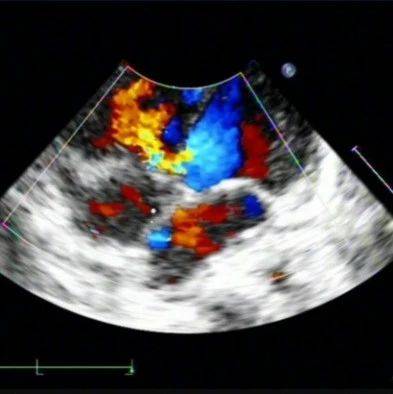

导语:PH影响患者的预后和移植选择,但通常易于接受治疗。来源:梅斯医学这项研究旨在确定双心室循环主动脉右心室(RV)成年患者(2V-RV)肺动脉高压(PH)(平均肺动脉压≥25mmHg)的患病率、预测因素、预后相关性和进展。分析了2000年至2018年在作者所在中心接受心导管检查2V-RV患者的回顾性数据。超声心动图评估肺动脉下心室压(左心室收缩压(LVSP))、年龄和B型利钠肽(BNP)作为PH筛选工具进行评估。Kaplan-Meier曲线分析了到达死亡、移植或心室辅助装置(VAD)复合结局的时间。分析来自重复导管检查的数据以评估PH随时间的变化,包括治疗的效果。共有141名患者(中位年龄39岁(IQR 33-45),68%男性)接受了191次心导管检查。在基线时,55%的患者有PH(单纯性毛细血管后PH 24%,毛细血管前和毛细血管后混合性26%和毛细血管前5%)。BNP(曲线下面积0.80; 95%CI 0.72至0.88; p<0.0001)与存在PH相关,而不是导管检查时的年龄或超声心动图估算的LVSP。短期随访期间(2.5(1.3-3.9)年),不存在PH和BNP<100pg/mL可以区分一个极低危亚组(p<0.0001)。利尿剂、米力农和VAD随着时间的推移改善了血流动力学。即使没有症状,PH在2V-RV患者中也很普遍。通过超声心动图很难识别PH,并且最重要的是,PH与不良结局密切相关。PH影响患者的预后和移植选择,但通常易于接受治疗。考虑到这些结果应降低侵入性血液动力学评估的门槛,并改变2V-RV失败患者的治疗。原始出处:Alexander Van De Bruaene. Pulmonary hypertension in patients with a subaortic right ventricle: prevalence, impact and management. Heart. 01 May 2019.